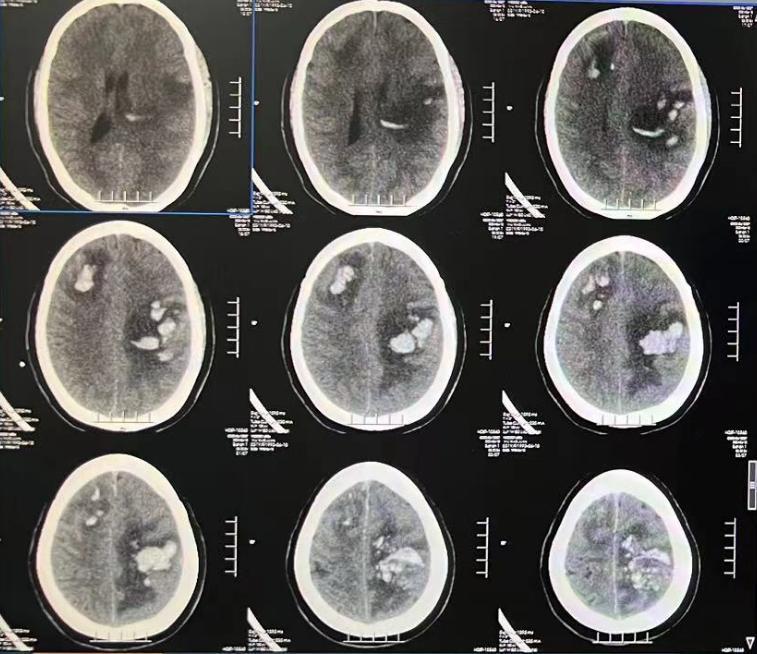

“患者入院时意识昏迷,情况危急,立即转入了重症医学科。”该院神经外十科欧阳辉教授介绍,患者是年轻产妇,颅内多发出血且形态不规则,并非是常见的脑出血,而是大静脉窦血栓导致脑静脉血液回流受阻,压力增高引起的淤积性出血。

影像提示:颅内多发出血且形态不规则

神经外十科及神经血管介入科急诊为患者行全脑血管造影。结果显示患者的上矢状窦、右侧横窦等颅内大静脉完全堵塞,证实是大静脉窦血栓。欧阳辉教授表示,虽然出血十分严重,但不能轻易开颅清除血块,应先对因治疗,疏通大血管(静脉窦)。否则患者的病情会持续恶化,危及生命。